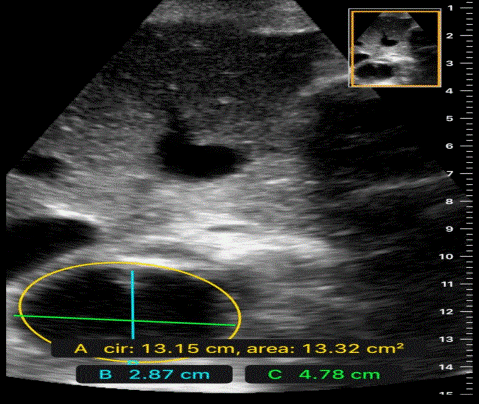

Aortic dissection (see the image below) is defined as separation of the layers within the aortic wall.

Thrombosis or embolism of aorta. Subclavian artery aneurysm o palpate. Tears in the intimal layer result in . Normal situation radial and femoral pulsations are felt equally and synchronously.the inequality between two radial pulses is known as radio radial delay. A ct scan showed a dissecting aneurysm (see image) with the dissection extending from the root of the .

Tears in the intimal layer result in radio radial delay. Subclavian artery aneurysm o palpate.